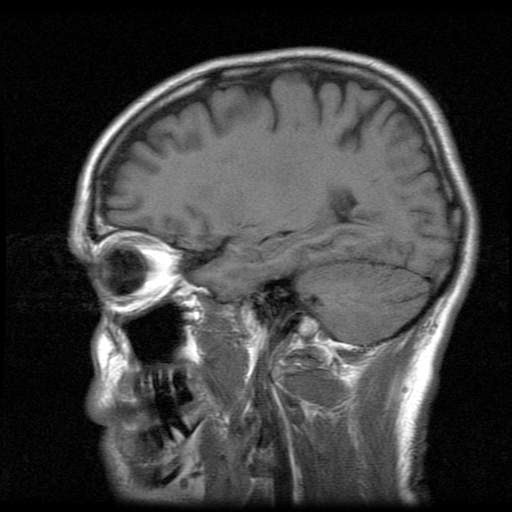

Nehemiah needed to have a MRI of his brain.

He had never had one before, but had another similar test,

which was a confining kind of test {similar to an MRI}

and surprisingly {haha} he didn’t enjoy the confinement.

He relaxed enough that he even fell asleep during much

of the 90 minutes of testing.

Then, of course, with Nehemiah’s wiggling as he breathed in his sleep

the doctor ordered a STAT

MRI with anesthesia for the very next day.